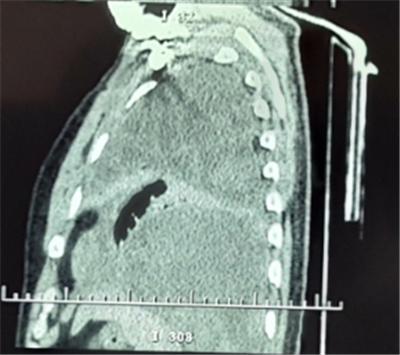

患者劉某,男性,52歲。因“胸悶、胸痛1月,發(fā)熱10余天”,就診于當(dāng)?shù)乜h醫(yī)院CT提示左側(cè)胸腔大量積液,予胸腔閉式引流同時(shí)抗感染治療,效果不佳遂轉(zhuǎn)入我院胸外科。復(fù)查胸部CT提示胸腔腫瘤合并胸腔積液。

入院后經(jīng)胸外科全體醫(yī)師對患者病情進(jìn)行綜合分析、積極術(shù)前準(zhǔn)備,于2月21日為患者實(shí)施手術(shù)治療。術(shù)中發(fā)現(xiàn)患者左側(cè)胸腔巨大腫瘤占位,體積約一個(gè)西瓜大小,幾乎完全占據(jù)了整個(gè)左側(cè)胸腔,左肺大部分被壓縮而失去功能,腫瘤與周圍組織粘連致密。切開腫物,其內(nèi)見大量魚肉樣物質(zhì)及黃色纖維素樣物質(zhì),取部分內(nèi)容物及腫物囊壁送檢冰凍切片,回示淋巴樣異型細(xì)胞。繼續(xù)游離,清除腫物內(nèi)容物,并予切除部分囊壁。

通過6小時(shí)的努力將腫瘤完全切除,出血約2000ml。術(shù)后病理檢查最終確診為胸腔尤文氏肉瘤。此種胸腔巨大腫瘤,手術(shù)難度大,術(shù)中出血多,手術(shù)風(fēng)險(xiǎn)高。